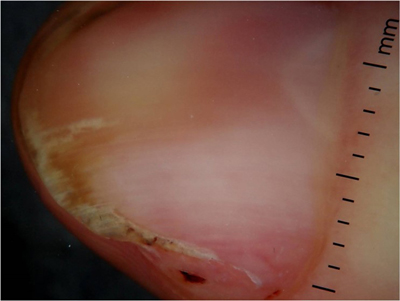

Onychopapillome (figure 1)Parmi les diagnostics différentiels de l’onychopapillome il faut désormais compter :– l’acanthome du lit [1] (ou nommé également kératose séborrhéique) avec des présentations variables : mélanonychie avec hyperkératose du bord libre, grains de milium, xanthonychie, leuconychie ou érythronychie plus rares. La figure ci-dessous monte le cas d’un patient de 54 ans. Le diagnostic différentiel principal dans ce cas reste la maladie de Bowen.– l’onychopapillome malin, publié par [...]